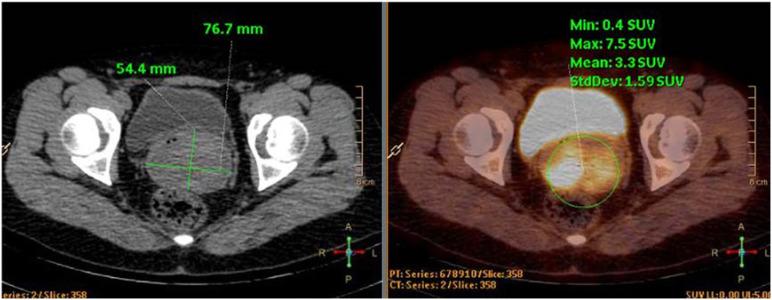

横纹肌肉瘤(RMS)是一种起源于原始间充质细胞的软组织肉瘤,这些细胞表现出不同程度的骨骼肌分化。尽管RMS主要影响儿童和青少年——是最常见的儿科实体恶性肿瘤之一——但在成年人中极为罕见,占成人癌症的比例不到1%。由于其胚胎间充质起源,RMS几乎可以在任何器官中发生。在成年人中,最常见的部位是躯干(27%)和四肢(26%),生殖道占17%。目前对成人胚胎性RMS的认识主要依赖于病例报告,因为它常常被误诊为其他良性或恶性实体肿瘤。在此,我们报告一例成年女性宫颈葡萄状RMS病例。诊断过程漫长;经过五次就诊和四次活检,最终确诊为横纹肌肉瘤。根据病理结果和影像学检查,临床分期确定为T1N0M0和国际横纹肌肉瘤研究组(IRS)IA期。患者最初计划在新辅助化疗后进行手术。然而,在一个化疗周期后,她出现大量阴道出血和宫颈息肉样肿物脱垂。由于严重的心理困扰,患者拒绝进一步化疗并坚持进行手术。随后,她接受了机器人辅助腹腔镜根治性子宫切除术、双侧输卵管卵巢切除术和盆腔淋巴结清扫术。术前和术后共进行了六个周期的VA化疗方案。不幸的是,术后8个月的随访结果不佳。手术后不到一年,盆腔增强MRI显示盆腔淋巴结肿大,提示可能复发。本研究的目的是报告一例成年女性宫颈胚胎性横纹肌肉瘤(ERMS)病例,并强调与该疾病相关的诊断和治疗挑战。